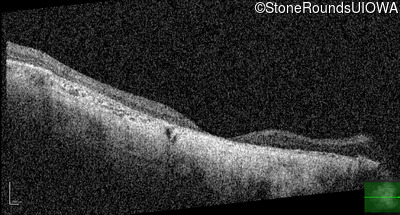

Age at visit: 43 years

OD OS